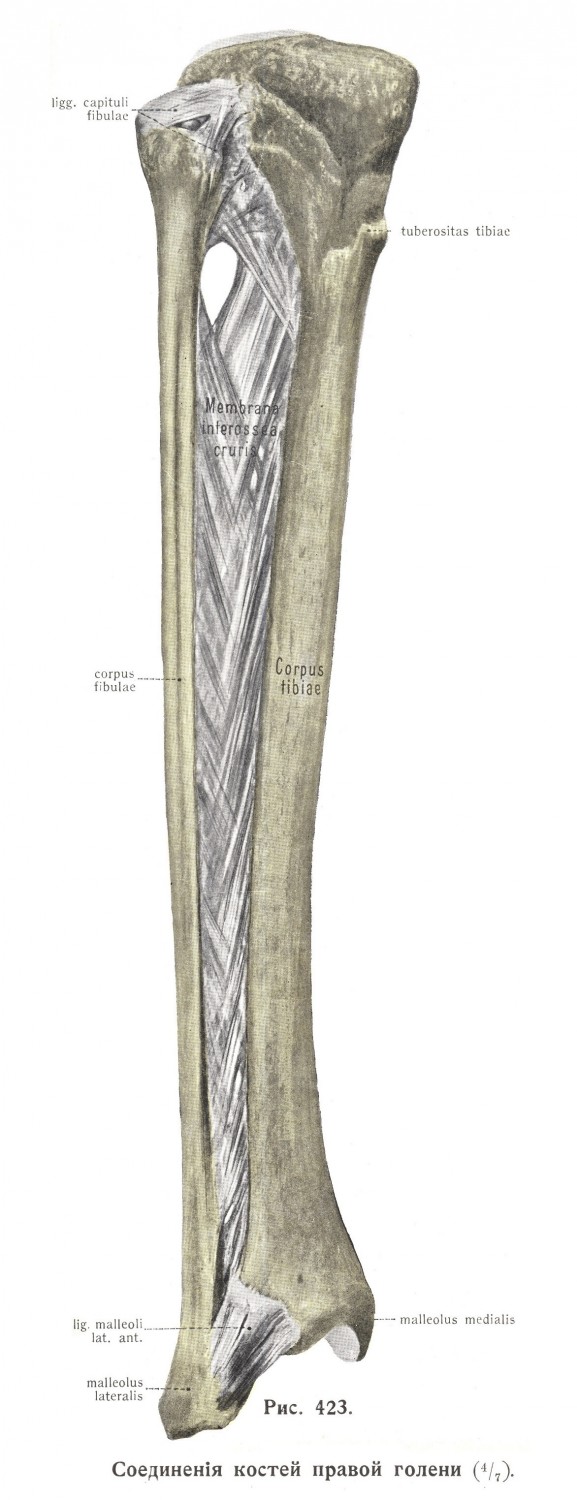

Структура и анатомия синдесмоза: научные иллюстрации